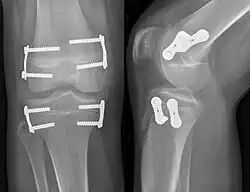

Epiphyseodese mit Zweilochplatten um die kniegelenksnahen Epiphysenfugen von Femur und Tibia zur Korrektur einer Beinlängendifferenz

• Zweilochplatte: Die modifizierte Plattenosteosynthese wird unter Röntgenkontrolle quer über die Wachstumsfuge eingebracht und an beiden Seiten der Fuge mit je einer Schraube fixiert. Dadurch wirkt die außen auf dem Periost aufliegende Platte wie eine Zuggurtung. Wie bei den Blount-Klammern kommt es durch Kompression der Wachstumsfuge zu einem Wachstumsstillstand im Bereich der Plattenosteosynthese.

Dieses Verfahren wurde erstmals 2006 von dem US-Amerikaner P. M. Stevens vorgestellt, er entwickelte die als Eight-plate bekannte und patentrechtlich geschützte erste spezielle Titan-Zweilochplatte ohne winkelstabile 4,5-mm-Schraubenverankerung für die Firma Orthofix. In den Folgejahren wurden mehrere Konkurrenzprodukte nach demselben Prinzip auf den Markt gebracht, teilweise sind die Schrauben winkelstabil verankert, teilweise nicht, z. B. PediPlate. Diese Technik hat sich binnen weniger Jahre durchgesetzt und wird inzwischen am häufigsten angewandt.